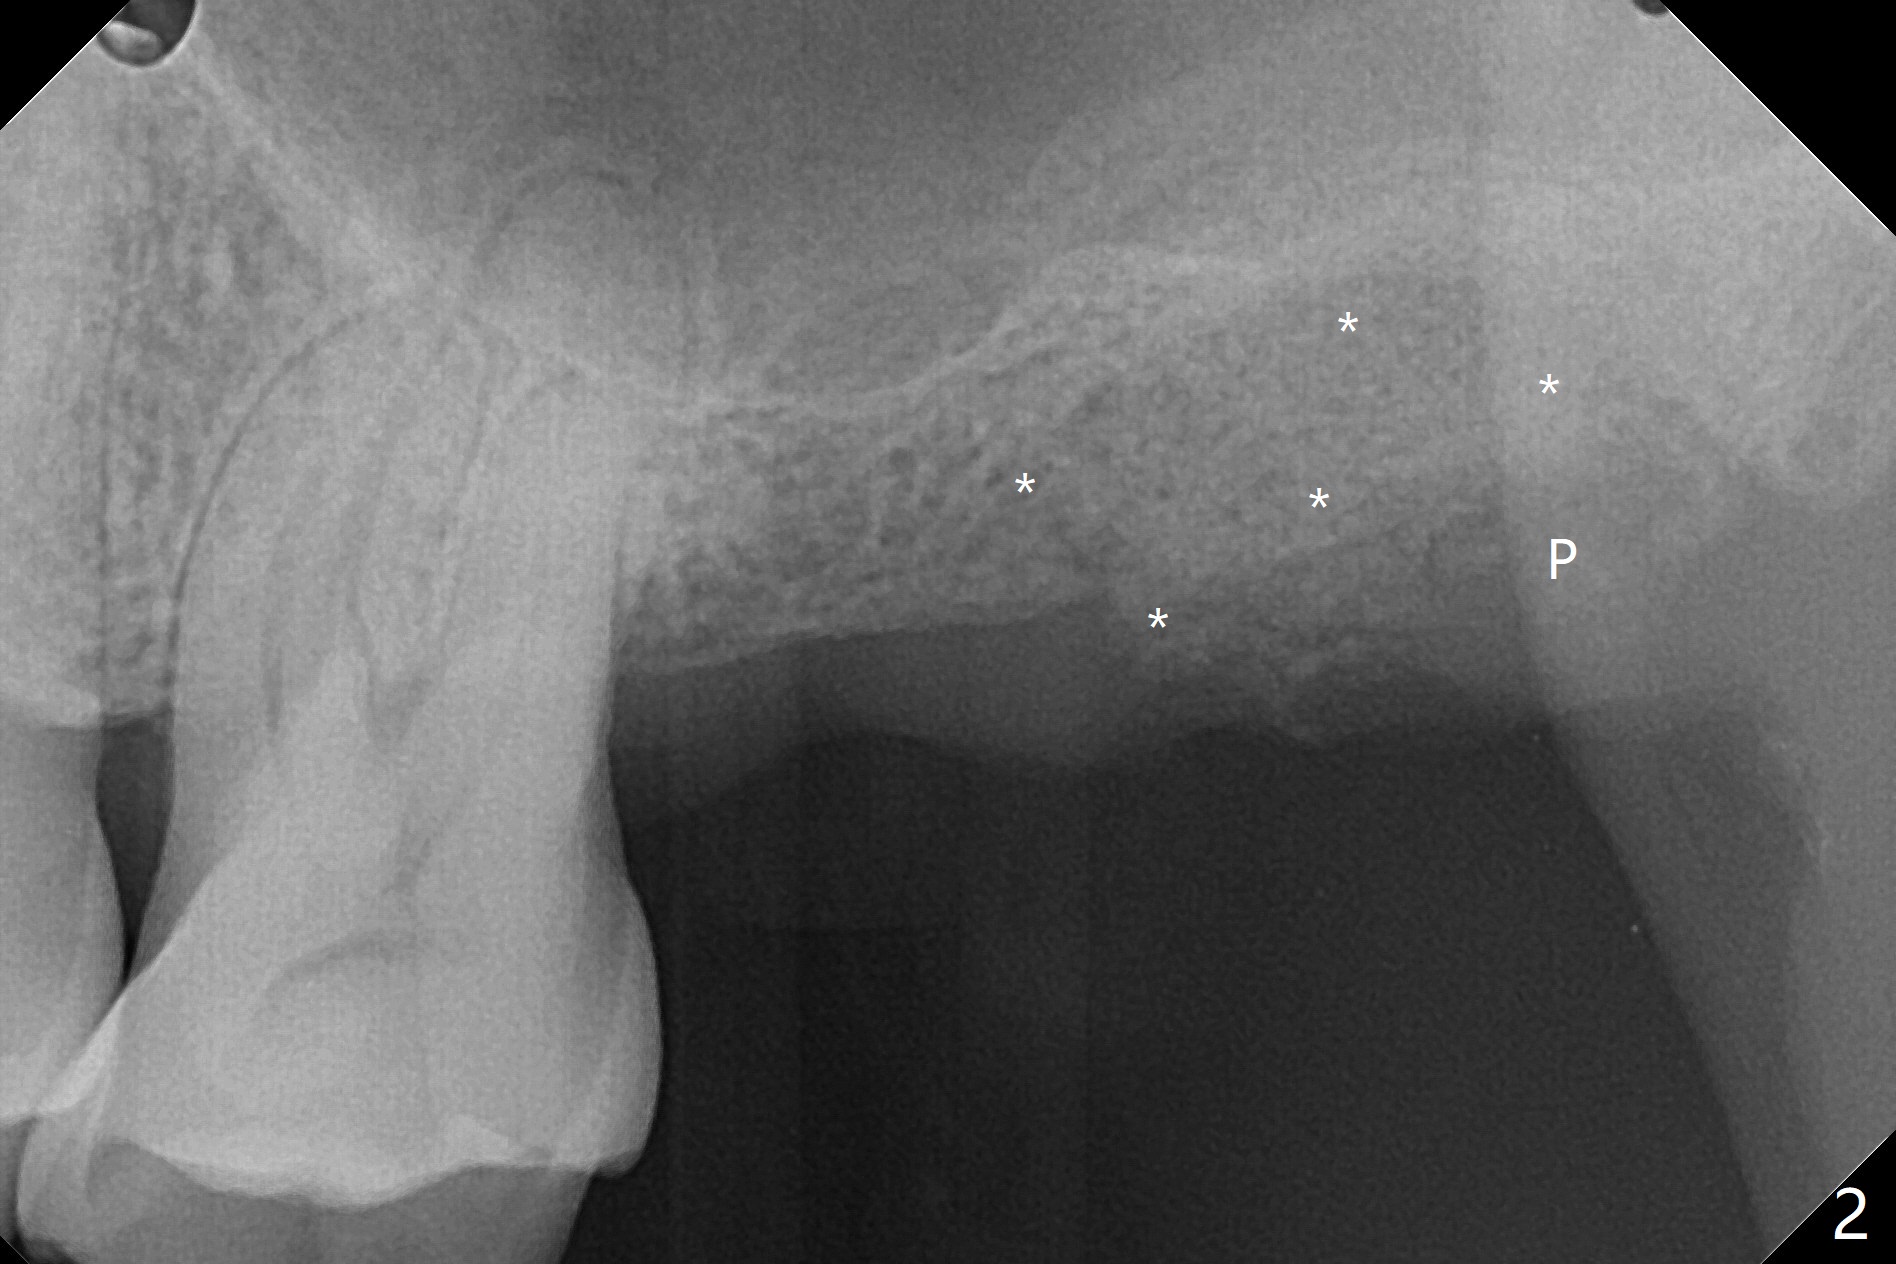

68岁男,缺失15号牙,由单颗牙局部托牙修复。当16号牙松动,近中移位,病人考虑拔除16号牙,经过讨论他同意在15号牙种植,治疗计划(图一)?17,18号牙存在。最佳方案:16号牙拔除(图一’:黑色),同期15号牙种植(绿色)。不过病人马上要出差,只好先拔牙(第二方案),需要植骨(图一”:圆圈)?其实需要植骨(图二:*),因为16号牙牙槽窝(图三:红虚线)侵犯15号牙植牙区(绿色)。植骨减少后期种植,植体螺纹远中螺纹暴露。